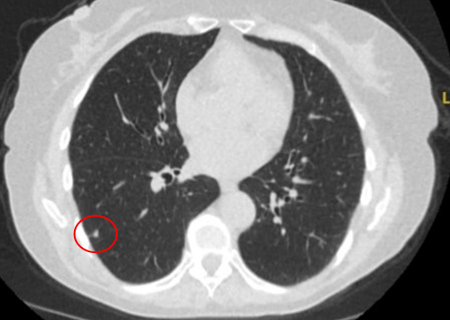

Tomografia computadorizada (TC) mostrando pequeno nódulo triangular periférico no lobo inferior direito, condizente com linfonodo intrapulmonar

Do acervo de Dr. George Tsaknis, MD, PhD, FRCP (Londres), MRQA, MAcadMEd, PGCert; usado com permissão